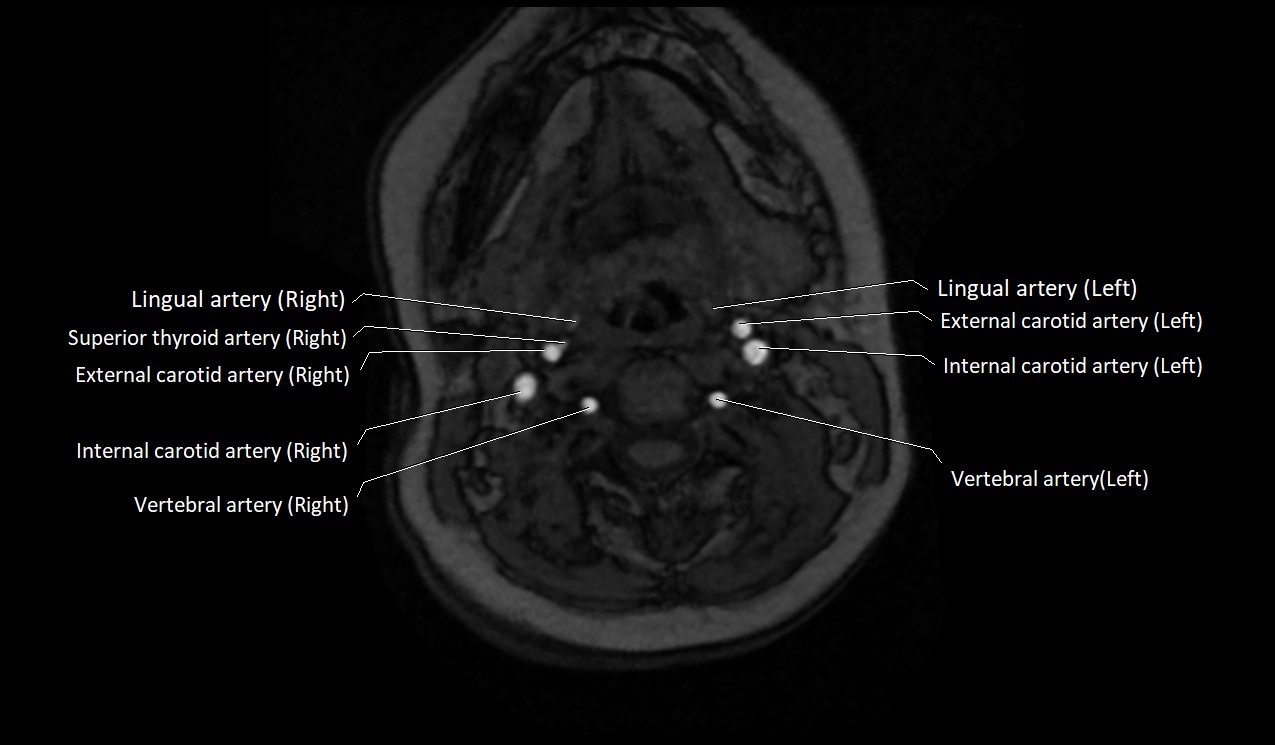

MRI images

image